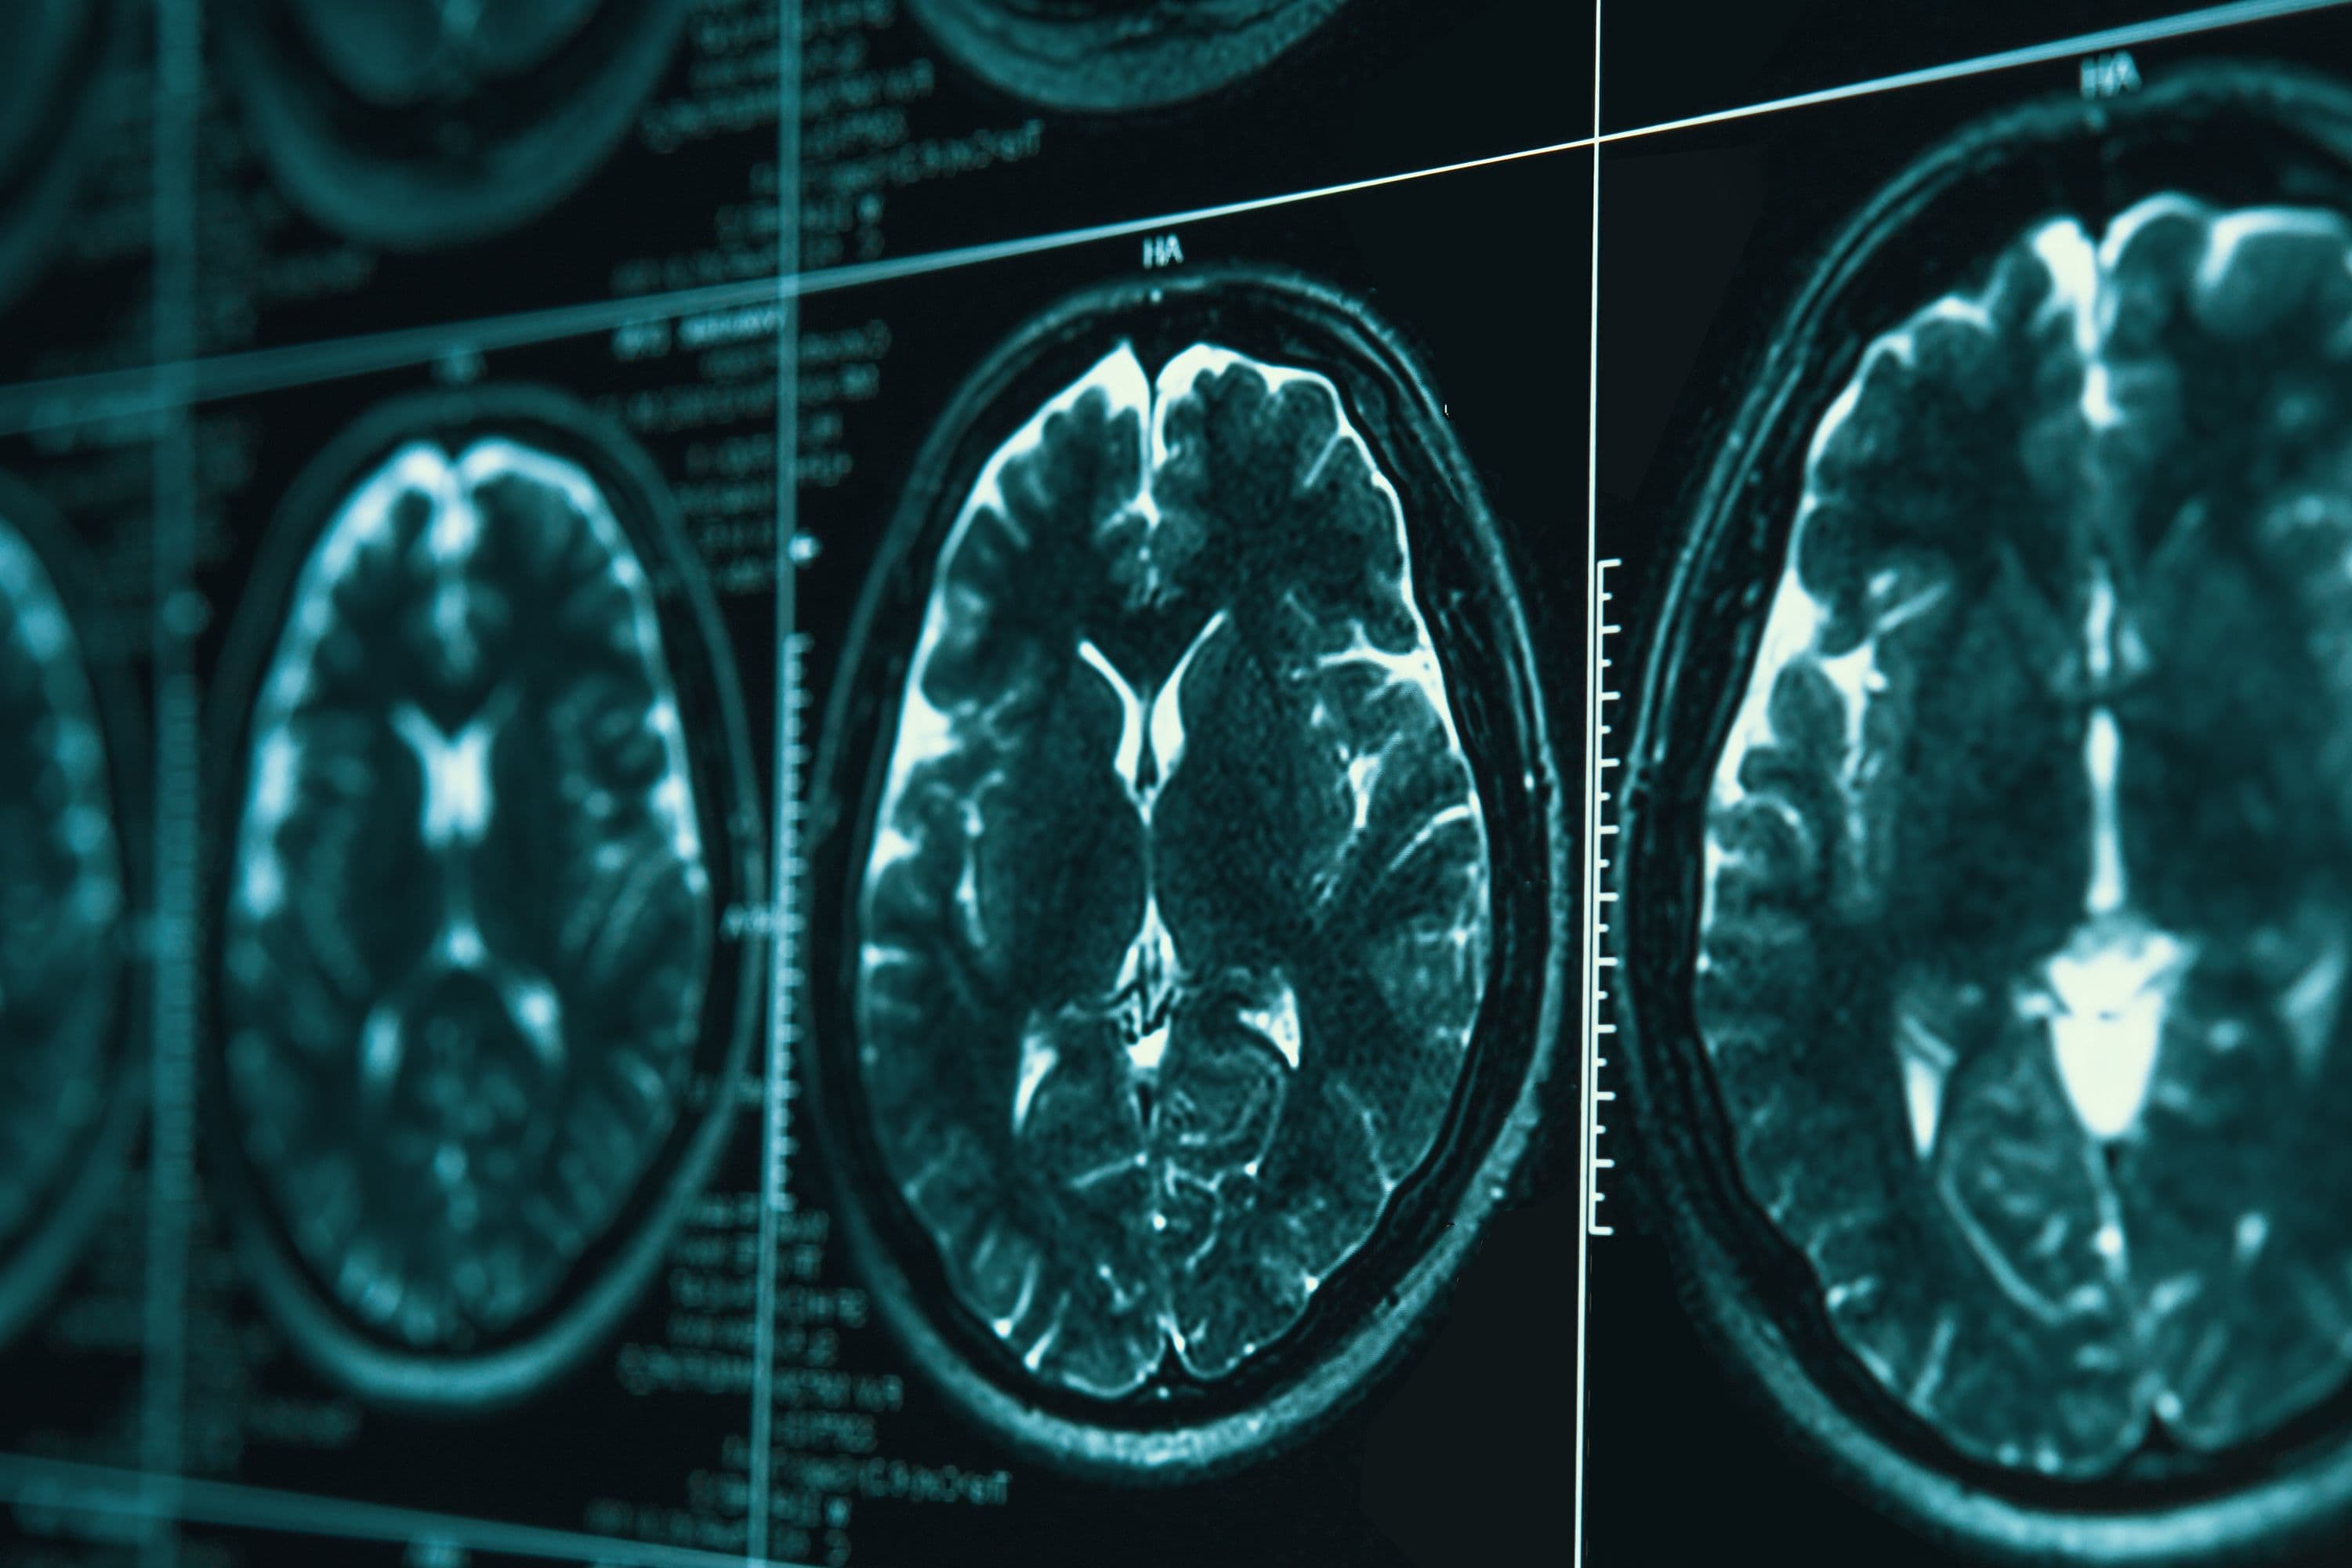

PRISM Imaging: Enhancing Detection of Neurological Disorders

Brain Mapping Solutions offers PRISM Imaging technology, enhancing the detection of TBIs, neurodegenerative diseases, and other neurological disorders for better patient outcomes.

Early detection of neurological disorders is critical for effective treatment. PRISM Imaging, a cutting-edge technology offered by Brain Mapping Solutions, enhances the ability to detect and analyze a wide range of neurological conditions, including traumatic brain injuries (TBI), seizures, and neurodegenerative diseases.

Detailed Explanation of PRISM Imaging

PRISM Imaging technology improves the accuracy and depth of brain scans, allowing for better detection and understanding of neurological disorders. It provides enhanced imaging for conditions such as CNS neoplasms, traumatic brain injuries, and neurocognitive disorders. This advanced neuroimaging tool helps medical professionals identify issues early, leading to better treatment outcomes.